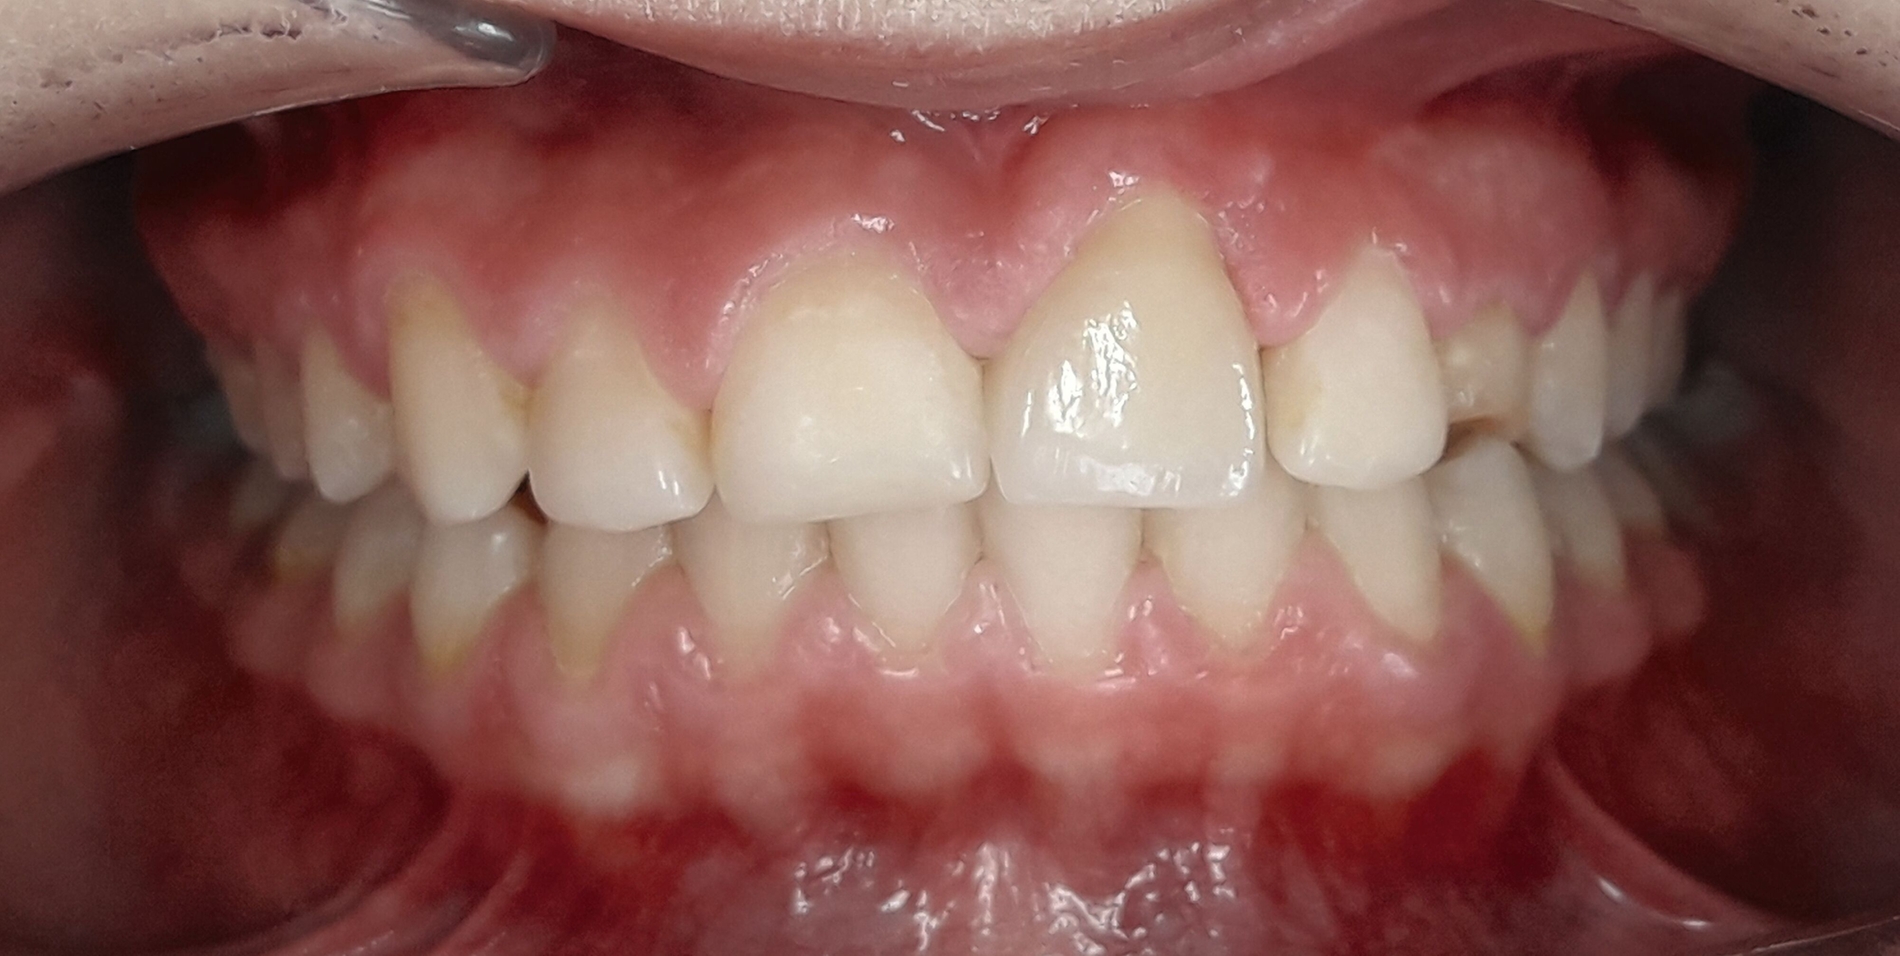

Im Februar 2019 wurde die kieferorthopädische Klinik von der Erstautorin übernommen. Bei der Auswertung der vorgefundenen Daten der Patientin wurde festgestellt, dass der linke obere zentrale Schneidezahn vor sechs Monaten extrahiert worden war. Die festsitzende Apparatur war im Oberkiefer bereits eingegliedert. Die Druckfeder zwischen Zahn 11 und 22 diente zur Lückenöffnung für den späteren prothetischen Ersatz des Zahnes 21. Auch auf den persistierenden linken Milcheckzahn war ein Bracket geklebt. Die Okklusion im Bereich der ersten Molaren war rechts und links neutral (Abbildung 2).